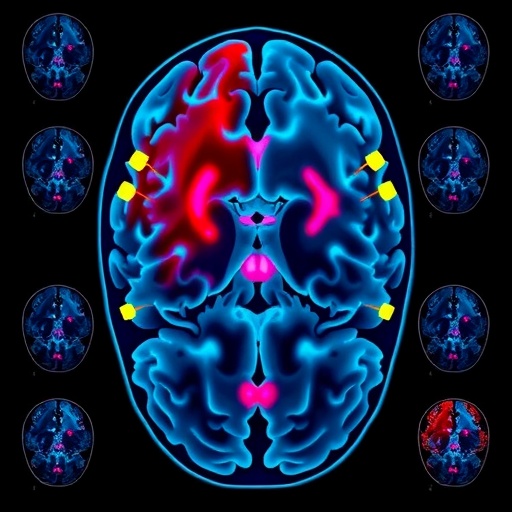

The researchers meticulously compiled data from dozens of resting-state fMRI studies, encompassing thousands of individuals with various psychiatric diagnoses alongside matched healthy controls. Through advanced statistical techniques and harmonized analytical frameworks, they examined alterations in connectivity within and between large-scale networks such as the default mode network (DMN), salience network (SN), and central executive network (CEN). These networks regulate self-referential thought, emotional salience, and cognitive control—the very pillars disrupted in mental illnesses.

One of the key revelations of the study is the consistent dysregulation observed in the DMN across psychiatric disorders. Typically active during rest and involved in introspection, self-referential processing, and memory, the DMN in affected individuals often shows hyperconnectivity or aberrant synchronization, which may contribute to rumination in depression or the distorted self-experience reported in schizophrenia. This finding aligns with theoretical models proposing that disrupted DMN activity underlies pervasive cognitive and affective symptoms.

Complementing these DMN changes, the salience network—which orchestrates attention and prioritization of relevant stimuli—was found to be hypoactive in several disorders. This hypoactivity compromises the brain’s ability to effectively flag emotionally significant environmental or internal cues, potentially leading to impaired emotional regulation and blunted affect seen in disorders like depression and schizophrenia. Altered connectivity within this network may also explain difficulties in shifting attention, a common cognitive deficit across psychiatric conditions.

Another critical insight is the variability found in the central executive network, responsible for higher-order cognitive functions such as working memory, decision-making, and cognitive flexibility. Across the psychiatric spectrum, reduced connectivity within the CEN was a frequent finding, suggesting a shared neural substrate for executive dysfunction. This impairment likely exacerbates challenges in planning, problem-solving, and impulse control, underscoring the neurocognitive symptoms that transcend diagnostic boundaries.

Importantly, the meta-analysis demonstrates that these network dysfunctions do not operate in isolation but reflect a broader imbalance in the brain’s functional architecture. The dynamic interactions between the DMN, SN, and CEN appear disrupted, flattening the adaptive switching mechanisms necessary for healthy cognition and emotion. The inability to transition smoothly between internally focused and externally directed processing modes may be a fundamental neural hallmark of psychiatric disease, offering a unified explanatory model.